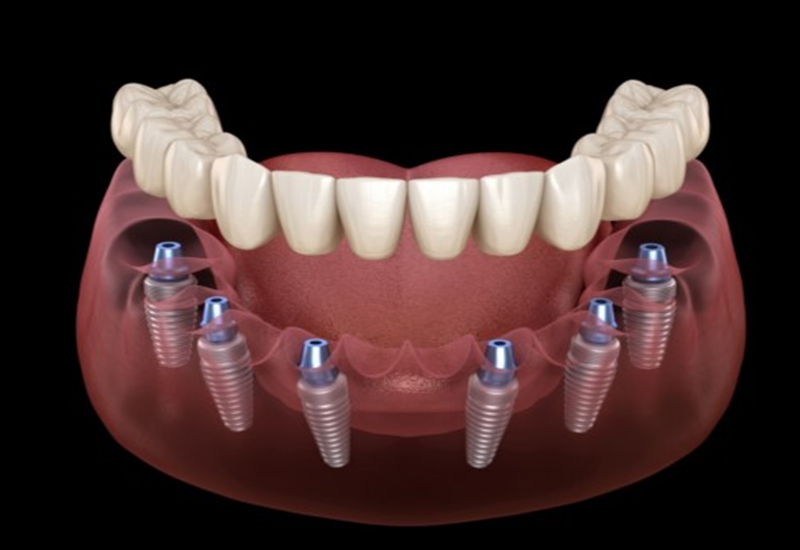

Trồng răng Implant là quá trình thay thế răng đã mất bằng một phương pháp nhân tạo. Nhằm khôi phục lại chức năng ăn nhai và thẩm mỹ cho hàm răng. Đây là phương pháp hiện đại, thay thế răng đã mất bằng cách cấy trụ titan vào xương hàm. Kết hợp mão sứ bên trên. Nó tạo nên một chiếc răng hoàn chỉnh – bền chắc, thẩm mỹ. Và hoạt động như răng thật. Trong số các kỹ thuật hiện nay, trồng răng Implant DCT được xem là đỉnh cao công nghệ. Giải pháp DCT mang đến kết quả vượt trội cho nụ cười của bạn! Hãy cùng khám phá các bước trong Quy Trình Trồng Răng Implant giải pháp DCT. Để hiểu vì sao đây là lựa chọn hàng đầu!

Sau khi hoàn tất quá trình lập kế hoạch trên phần mềm. Một máng hướng dẫn sẽ được sản xuất nhằm mục đích đặt trụ implant chính xác. Tránh làm tổn thương các cấu trúc lân cận, tổn thương ống dây thần kinh răng dưới hay xoang hàm… Đồng thời, mô nha chu cũng được tái lập giả định trên trạng thái lý tưởng. Sau đó một trụ lành thương giải phẫu cá nhân hóa sẽ được sản xuất cùng với máng hướng dẫn.